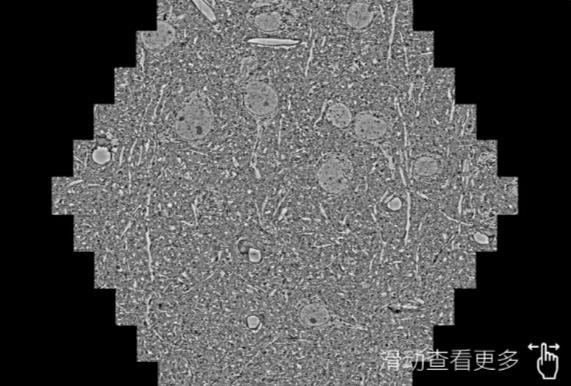

鼠脑切片。左图使用平凉蔡司平凉扫描电镜MultiSEM706对165μmx143pm面积区域成像,耗时仅需1.5秒。右图为鼠脑切片中30μm区域放大效果。样品由芝加哥大学B.Kasthuri提供。